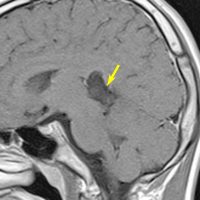

なぜ脳幹部からの無理な剥離が必要な手術を勧めるか

30歳くらいの時に初回の開頭手術で部分摘出を受けて,現在70代の患者さんの画像です。黄色は今も残っている腫瘍です。2度目の開頭手術,3度目の開頭手術では癒着で脳幹部や脳神経からの剥離が全くできませんでした。現在でも脳幹部に入り込むように腫瘍がゆっくり大きくなっていて,体幹失調のために車椅子生活です。顔面神経麻痺,嚥下障害,構語障害,眼球運動障害などもあります。髄液吸収障害による水頭症を併発してシャント手術も受けています。

この患者さんの40年の経過はいろいろなことを教えてくれます。似たような患者さんをたくさん見てくると,初回手術で取りきれなかった類表皮のう胞を,2度目の開頭手術で完全摘出することはとても難しいという経験を積みます。

数十年後のことを考えるのであれば,初回手術で完全摘出するべきです